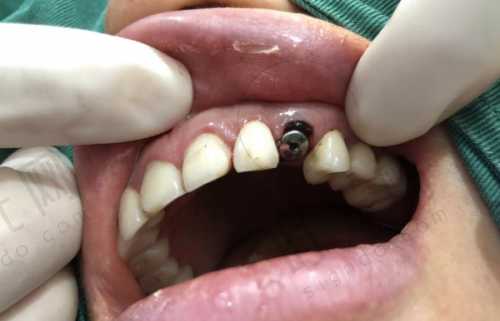

全方面检查:在进行种植牙手术前,患者需要进行全方面的口腔检查和身体检查。包括口腔X光片、CT 扫描等,以确定牙槽骨的情况和身体是否适合种植牙手术。如果有高血压、糖尿病等全身性疾病,需要先将病情控制稳定后再进行手术。